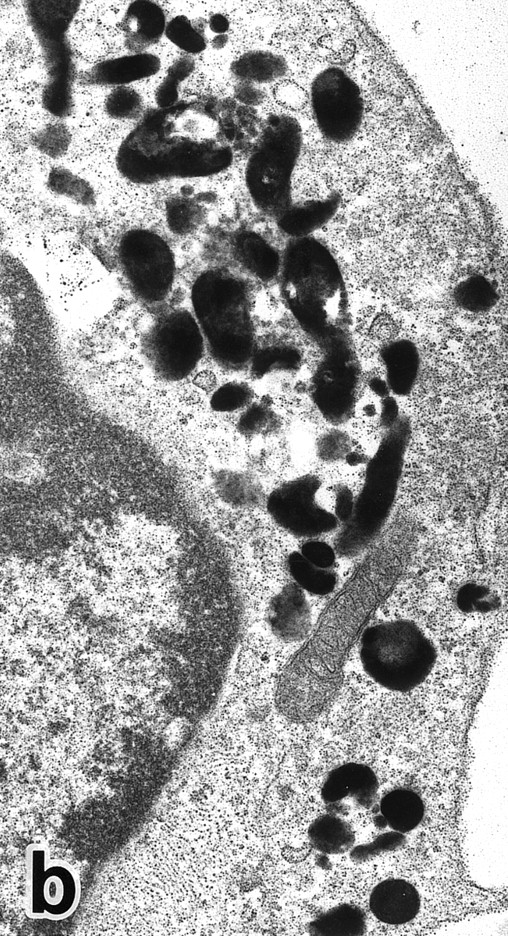

APL cells in culture.APL cells in patient no. 3 were cultured in the presence of ATRA or G-CSF for 7 days, and their morphological changes were examined under a light microscope. After 5 days of culture with ATRA the cells displayed a tendency toward maturation, including nuclear lobulation, chromatin condensation, and a decrease or disappearance of azurophil granules, similar to that observed in bone marrow cells. The cells cultured with G-CSF for 7 days, on the other hand, retained a promyelocytic appearance with numerous azurophil granules that even seemed to have increased in size and/or number (data not shown). Electron microscopic examination showed the nuclei of the cells cultured with ATRA to be irregularly lobulated with marginally condensed heterochromatin and the lobulated nuclei to be often connected by nuclear filamentous structures, in a manner similar to the cells seen in the bone marrow (Fig 8). These cells contained numerous MPO-positive primary granules, including irregularly shaped granules, but no MPO-negative specific granules were identified.

(a) A PMN that emerged in the APL cell culture of patient no. 3 in the presence of ATRA for 1 week. From the lobulated nuclear configurations and condensed heterochromatin, this cell looks like a PMN. However, the cytoplasm contains many MPO-positive primary granules but no secondary granules. (MPO-stained section, original magnification × 14,900.) (b) Higher magnification of a portion of the cell in (a), showing that the cytoplasmic granules are all MPO-positive. (MPO-stained section, original magnification × 30,100.)